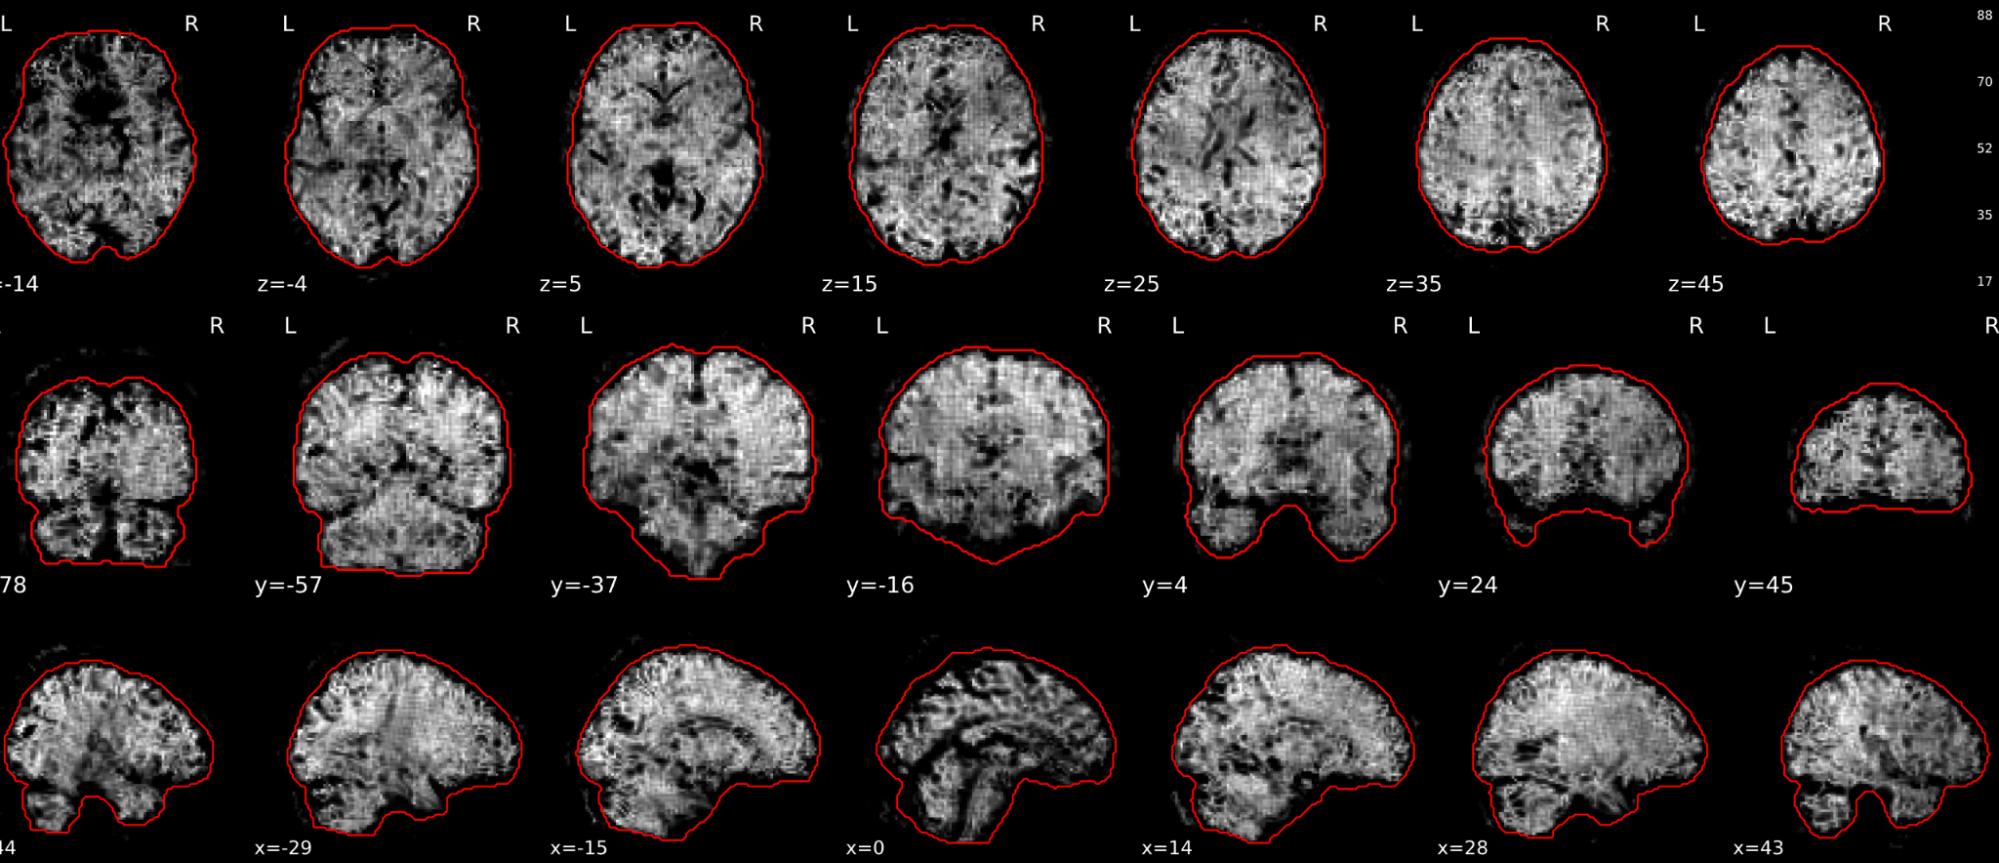

EPI tSNR

In the signal to noise ratio images of the resting state image the desired signal is compared to the amount of background noise. It is important to check all the views (sagittal, coronal, axial) because some artefacts (e.g., stripes) may be evident only in one particular view.

Example of a good subject

- Signal to noise is symmetrically distributed and there is no signal distortion

Example of a bad subject

- Asymmetry

- Potential signal distortion (might represent an artefact)

- Signal drop-out

- Stripes artefact

Clear large artefact (e.g., zebra stripes in example 1) are worth the exclusion of the subject. If you are unsure, check the other quality metrics for that subject to decide whether they should be excluded.

Summary

| good | bad |

|---|---|

| Symmetrical distribution of noise and signal | Asymmetry |

| No disruptions of the signal (no “black patches”) |

Potential signal disruptions (could be related to artefacts) |

| No stripes (sign of high motion) |

Signal drop |

| Stripe artefacts (“zebra” stripes due to motion) |